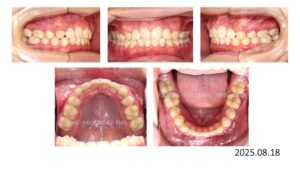

治療終了時の写真です。

動的治療期間は、1年 5か月です。

上顎前歯は 8㎜、下顎前歯は 4㎜後退し、口が閉じれないという主訴も改善されました。